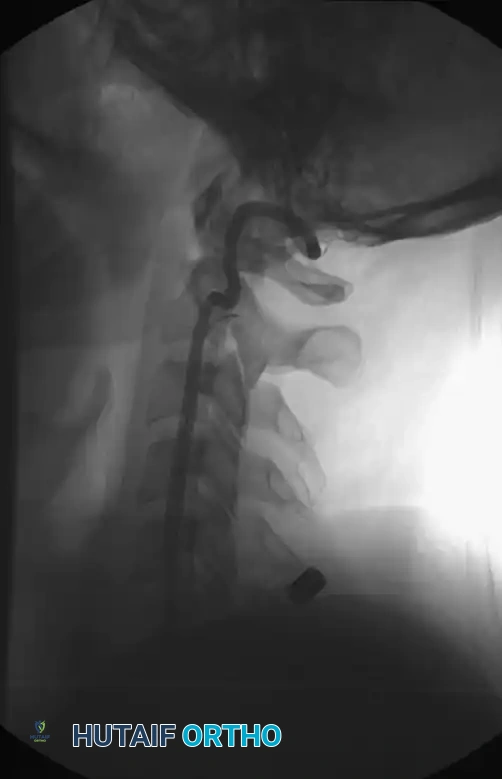

Plain Radiography

When utilizing plain films, the lateral cervical spine radiograph must visualize the entire cervical spine down to the superior endplate of T1. The most frequently missed cervical spine fractures on plain radiographs occur at the extremes of the cervical spine: the odontoid process (C2) and the cervicothoracic junction (C7-T1). If T1 cannot be visualized due to shoulder shadow, a Swimmer's view or, preferably, a CT scan is mandatory.

Prevertebral Soft Tissue Swelling:

Weir established classical criteria for evaluating the cervical spine, highlighting the prevertebral soft-tissue shadow. Historically, this shadow should not exceed 5 mm in width at the anteroinferior border of C3. A width exceeding 5 mm suggests hemorrhage and edema secondary to a fracture or ligamentous disruption.

However, modern evidence has challenged the reliability of this metric. Herr et al., in a study of 212 patients, demonstrated that prevertebral soft-tissue measurement at C3 is an insensitive marker for cervical spine fractures or dislocations and does not reliably correlate with the location or mechanism of injury. Furthermore, the loss of the normal cervical lordotic curve is often due to muscular spasm and is not, in isolation, definitive evidence of structural injury.